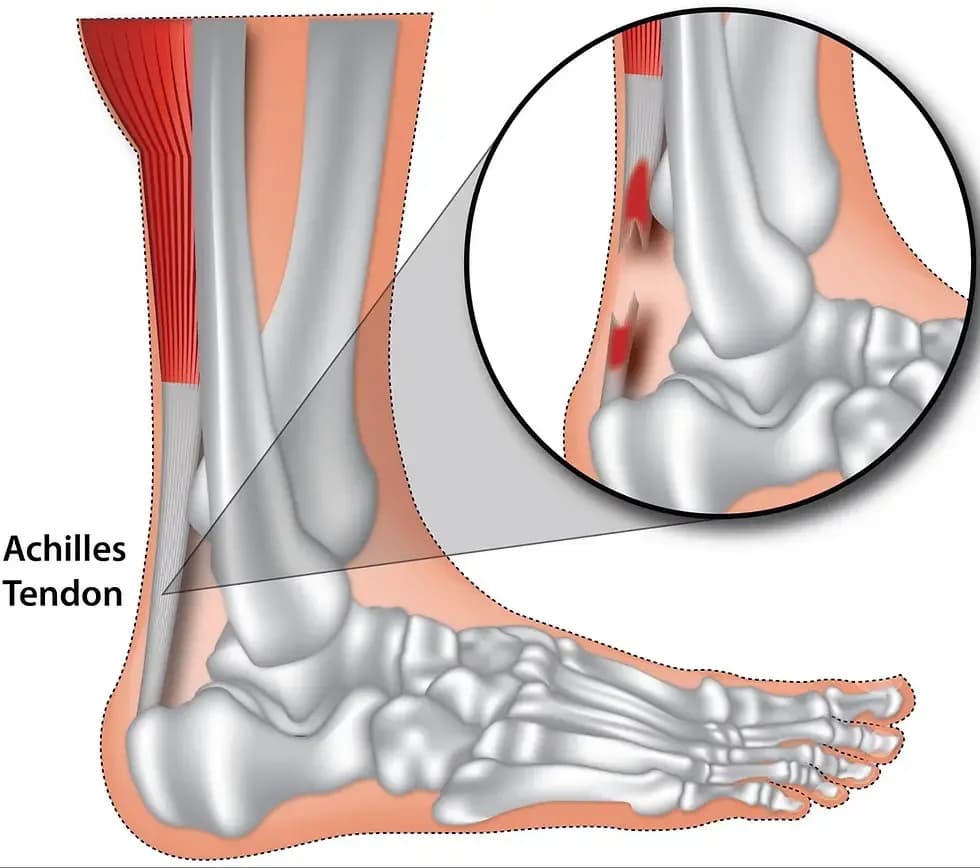

Aşil Tendonu Yırtığı Nasıl Tedavi Edilir?

Aşil tendonu yırtığı, en çok 30-40 yaşları arasında görülmektedir. Erkeklerde kadınlara oranla 5 kat daha fazla...